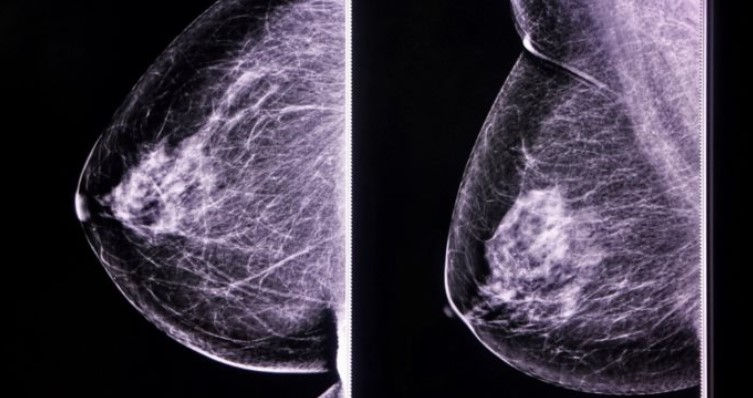

MAMOGRAFIA

La mamografía digital es la técnica principal para el diagnóstico de las lesiones mamarias y en la que se tiene una mayor experiencia en la actualidad. Es una radiografía de la mama que se realiza con equipos específicamente diseñados, denominados mamógrafos.

Para obtener las imágenes de la mama mediante la mamografía se utilizan radiaciones ionizantes, por lo que no es una exploración completamente inocua. A lo largo de varias décadas, la mejora de los equipos de mamografía ha hecho posible pasar de mamógrafos llamados “analógicos”, en los que las imágenes se recogían físicamente en placas o radiografías, hasta mamógrafos “digitales”, en los que las imágenes se estudian en monitores específicamente diseñados. De forma paralela, la cantidad de radiación necesaria para obtener estudios mamarios de alta calidad, también ha disminuido de forma notable.

Actualmente, la mamografía digital es la técnica estándar para el estudio de la mama. El estudio de las imágenes digitales en monitores de alta resolución, permite evaluar la mama con unos niveles de detalle y calidad muy elevados.